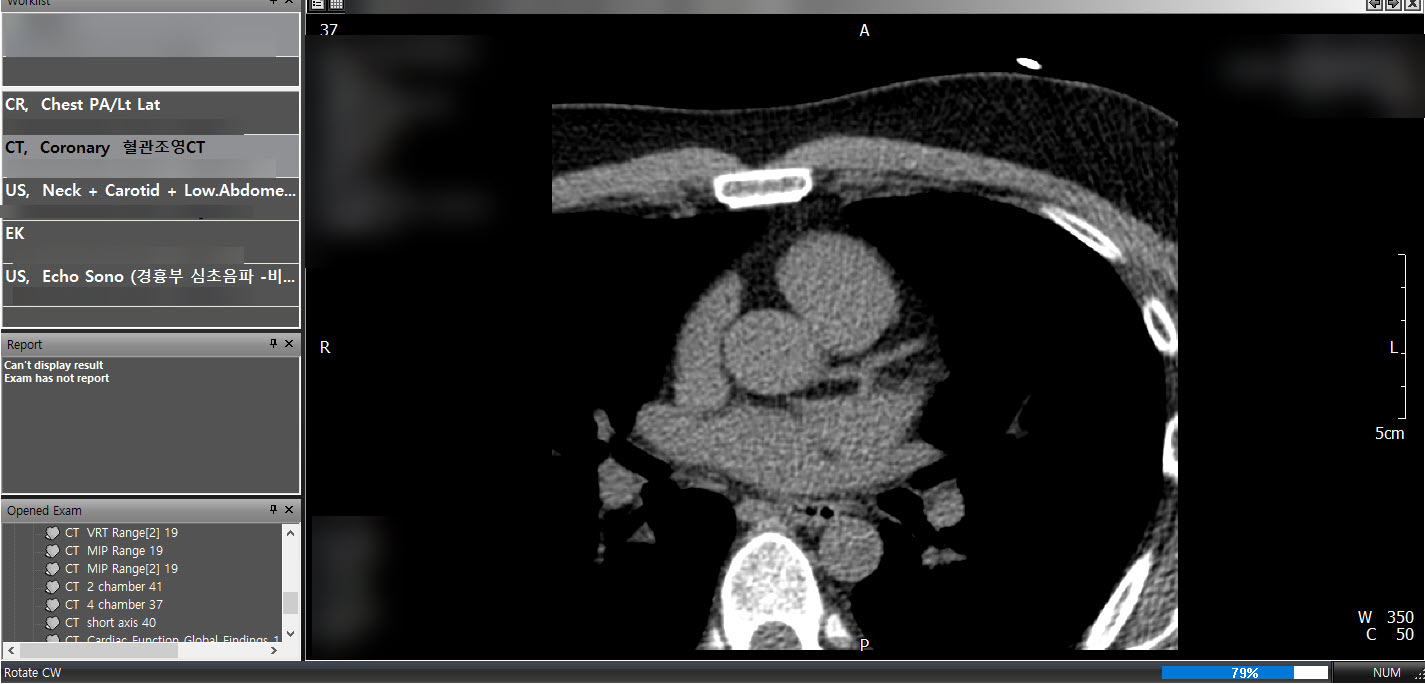

PACS는 CT, MRI와 같은 의료영상장비를 사용하여 촬영된 이미지(DICOM형식)를 저장, 가공, 전송할수있는 시스템이다. 의사는 PACS viewer를 통하여 영상을 판독하고 환자의 상태를 진단할수있다. 다양한 종류의 PACS 뷰어 프로그램이있으며 PacsPlusCV는 PACS 뷰어의 일종이다.

프로그램을 실행하고 의료용 디지털 영상 포맷인 DICOM파일(.dcm)을 불러오기하면 촬영영상 이미지를 확인할수있다.